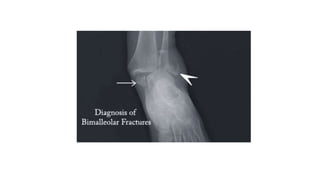

TYPES OF ANKLE FRACTURE & DISLOCATION

• BIMALLEOLAR:

• means that two of the three parts or malleoli of the ankle are broken.

• In most cases of bimalleolar fracture, the lateral malleolus and the medial malleolus are broken

and the ankle is not stable.

• A "bimalleolar equivalent" fracture means that in addition to one of the malleoli being fractured,

the ligaments on the inside (medial) side of the ankle are injured. Usually, this means that the

fibula is broken along with injury to the medial ligaments, making the ankle unstable.

• A stress test x-ray may be done to see whether the medial ligaments are injured.

• Bimalleolar fractures or bimalleolar equivalent fractures are unstable fractures and can be

associated with a dislocation.